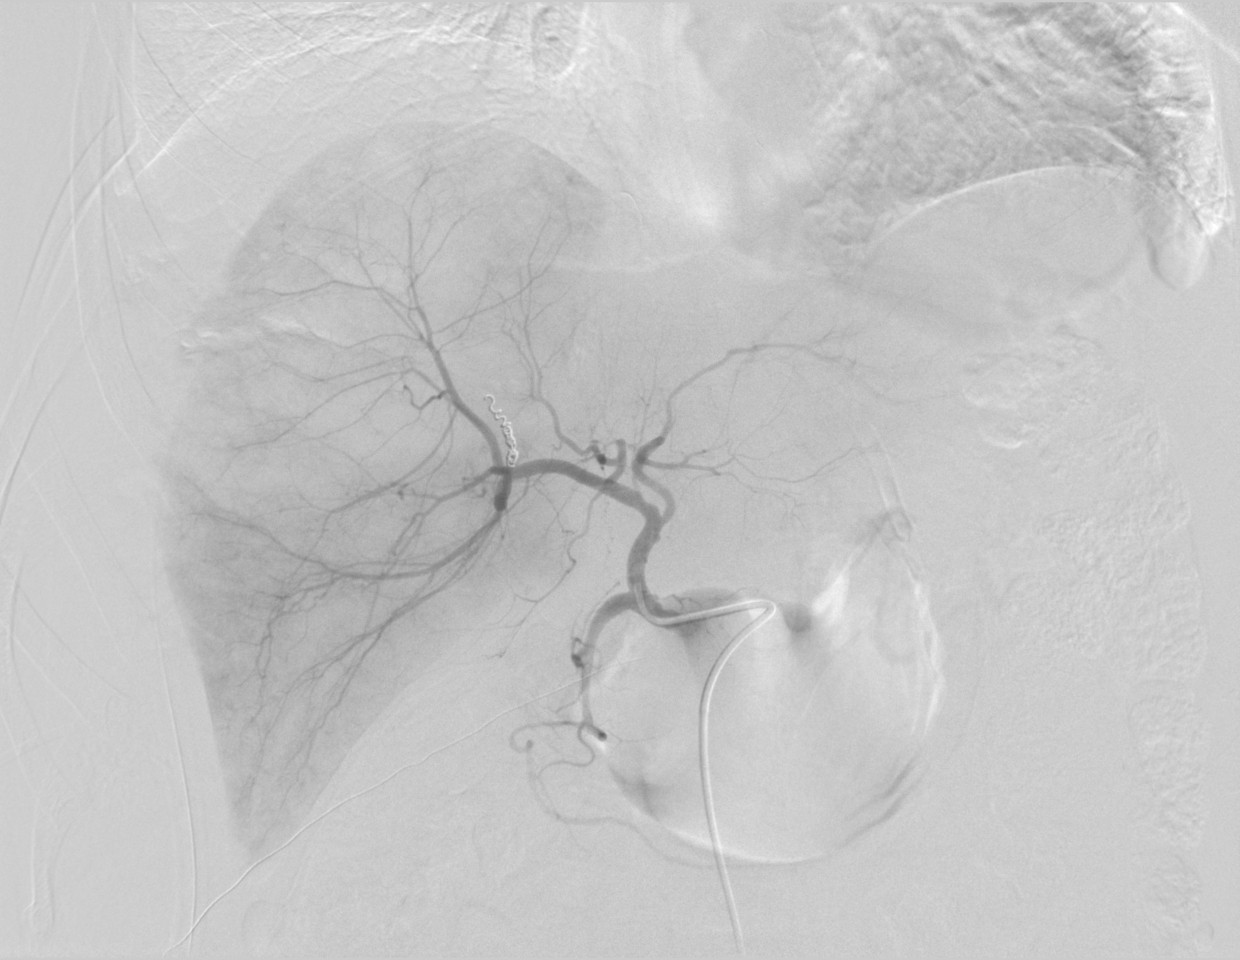

急診外傷肝破裂的介入治療

治療前

治療后